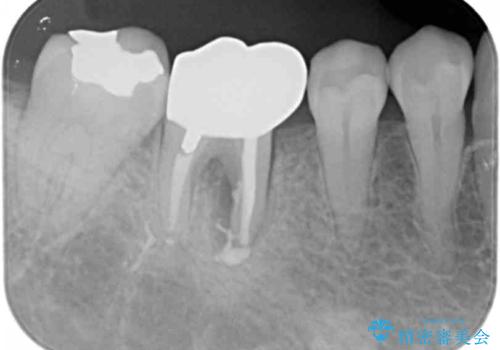

また、根の詰め物が根尖孔外(根の先の外の骨の部分)に盛大に漏れ出しており、歯周ポケットと根尖病巣が交通しているような状態でした。

被せ物を外したところ、歯が大変薄くなって割れており、残念ながら残すことはできないと説明しました。